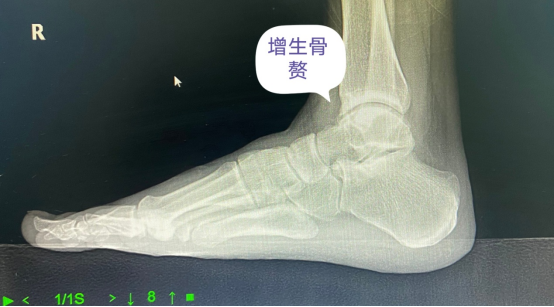

近日,家住广州海珠区的于女士跳完广场舞后大踇趾像被压了一样的疼痛,红肿明显,无法穿鞋行走,随即来到我院找到了骨伤科徐楚江主任医师就诊。